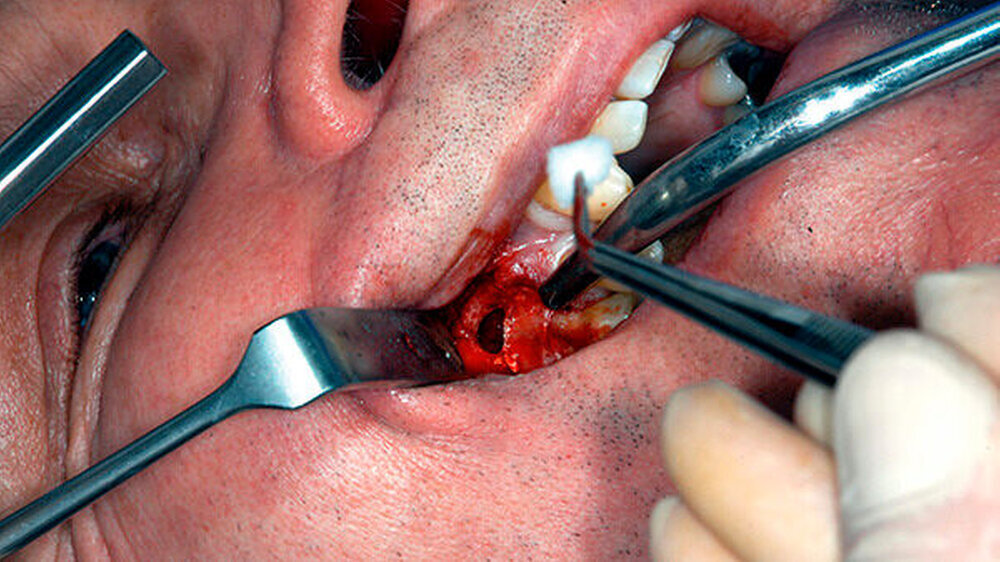

Um die mesiobukkale Wurzel freizulegen, wurde der Knochen darüber entsprechend entfernt (Abbildung 2) und eine Wurzelspitzenresektion an der mesiobukkalen Wurzel Zahn 16 durchgeführt. Das Granulationsgewebe konnte vollständig entfernt werden und wurde für eine histopathologische Untersuchung eingeschickt.

Mit einem ultraschallgetriebenen diamantierten, abgewinkelten Instrument wurden beide Wurzelkanäle der mesiobukkalen Wurzel von retrograd präpariert (Abbildung 3). Das frakturierte Instrument konnte so dargestellt (Abbildung 4) und entfernt werden.